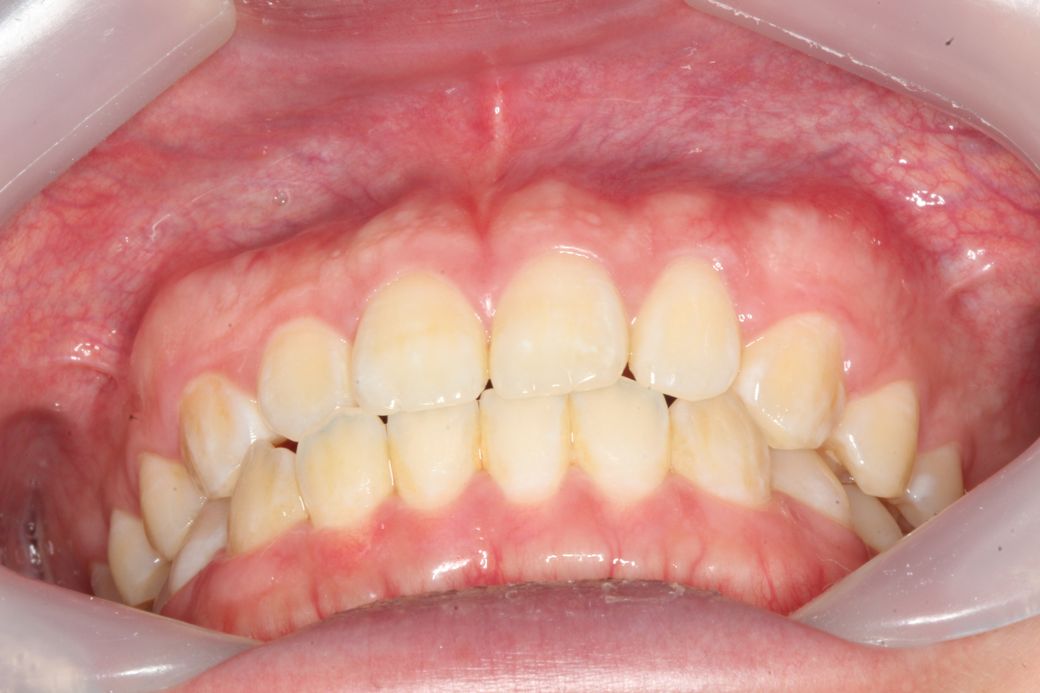

치과에서 사진찍었는데 사진을 보니 잇몸이 돌출된 느낌이 들어서요 치아 각도는 정상같아 보이는데 잇몸이 전체적으로 앞으로 쏠린느낌이 듭니다

잇몸이 전방돌출 된 것 일까요?

이정도는 정상범주에 속합니다. 잇몸뼈가 약간 두껍고 약간 앞으로 나오긴 했지만 건강한 잇몸과 잇몸뼈

상태입니다. 이것 때문에 나중에 잇몸 건강에 나쁜 영향을 주지는 않습니다.

잇몸 돌출도 아니며 정상입니다. coral pink의 정상적인 잇몸 색이며 잇몸의 모양은 사람에 따라 다르며 치조골의 두께도 다를 수 있습니다. 따라서 현재의 정도는 비정상적이라고 하지 않으며 이를 치료해야 하는 질병도 아닙니다.